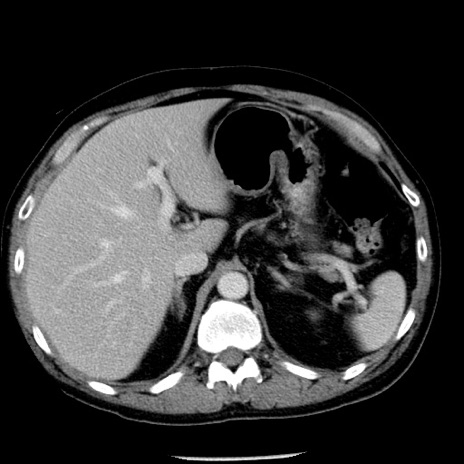

症例29(横断像)

【症例】40歳代男性

【現病歴】2日前から胃痛あり。徐々に周期的な激痛に変化した。本日になっても激痛があるため受診。

【身体所見】意識清明、BT 38-39℃台あり、腹部:膨満、やや硬、右下腹部に圧痛あり。

【データ】WBC 8500、CRP 23.26